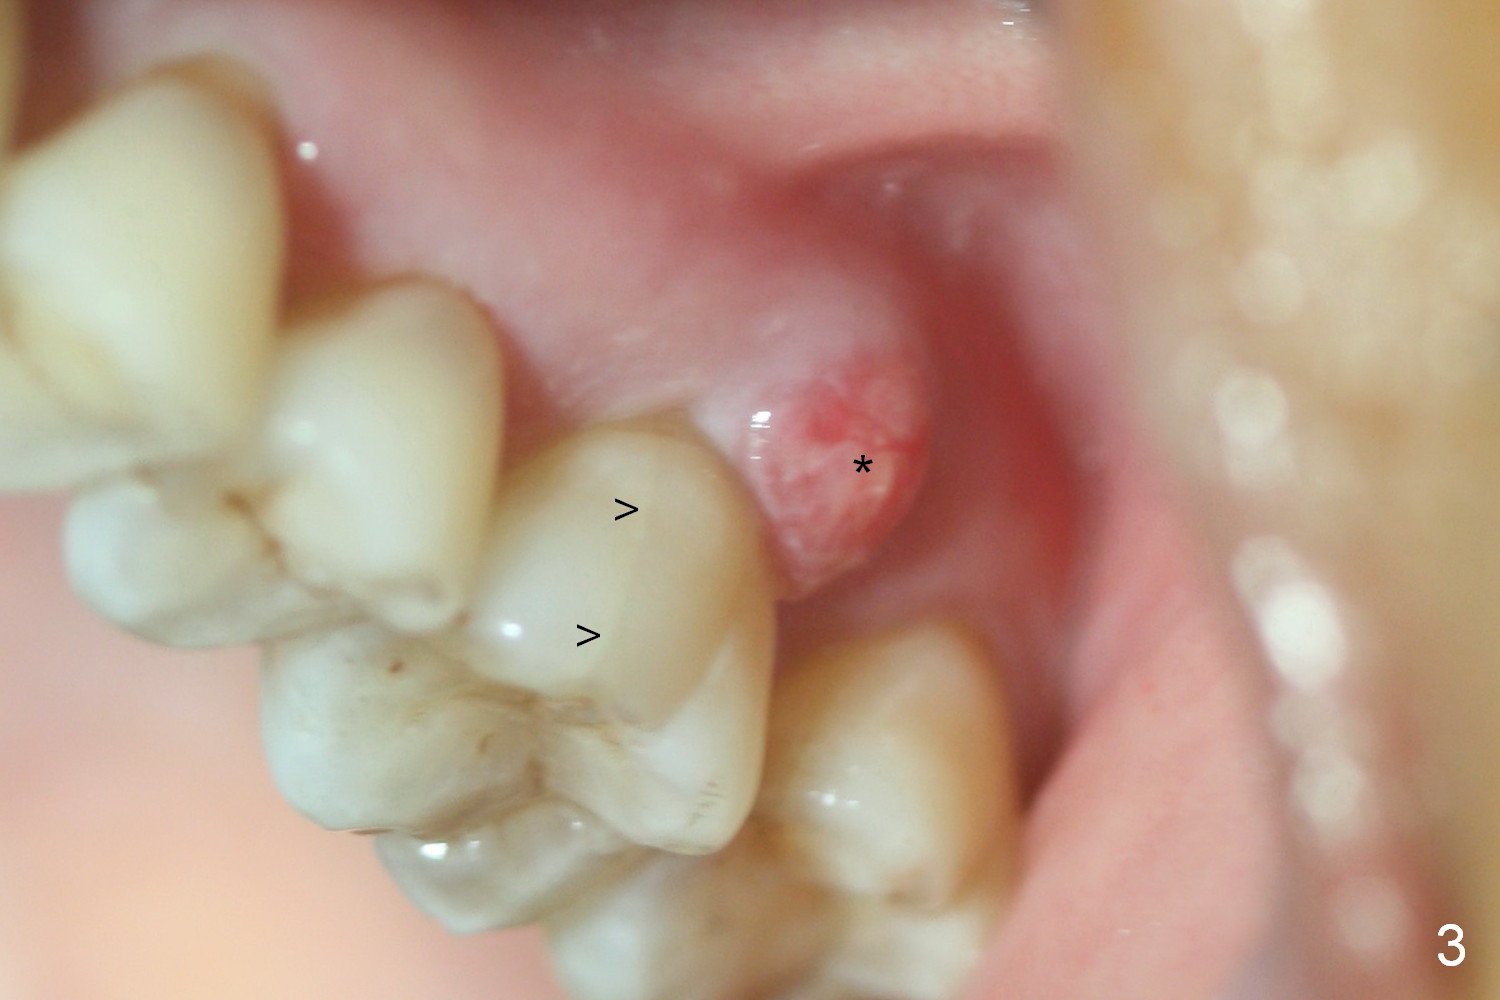

Approximately 2 months ago, the patient had vague pain in the upper left quadrant. The tooth #15 appeared to have crack tooth syndrome. Recently she developed severe pain and saw a periodontist. When she returns to our office, there is an obvious crack line lingually (Fig.1 <) with a nearby abscess (*). The crack line happens to be visible in X-ray (Fig.2 black <). The buccal abscess is larger (Fig.3 *); more surprising is hardly visible mesiobucal crack line (>).